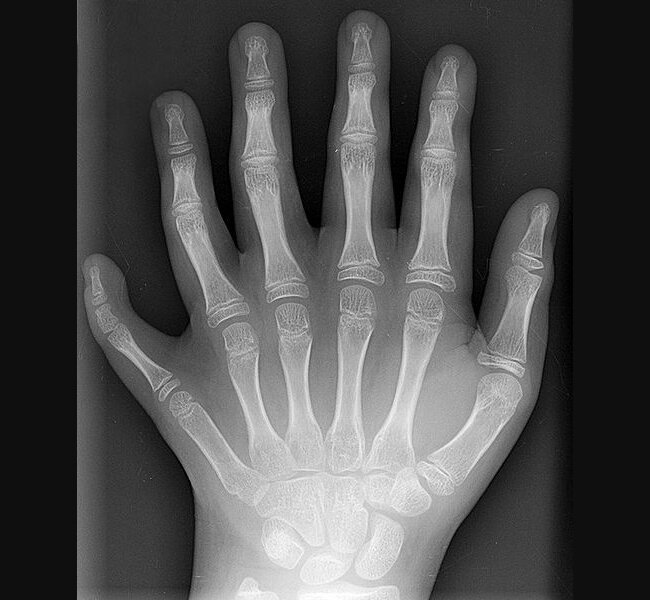

Рентгеновский снимок шестипалой левой руки 10-летнего ребёнка. (Creative Commons https://en.wikipedia.org/wiki/File:Polydactyly_01_Lhand_AP.jpg)

В науке шестипалость называется полидактилия. Есть несколько классификаций. Ученые выделяют три вида в зависимости от того, где расположен дополнительный палец: дополнительный большой палец, дополнительный мизинец и наиболее редкая форма - удвоение одного из средних пальцев.

Еще полидактилия очень редко бывает функциональной, когда дополнительные пальцы такие же как здоровые. Дополнительные пальцы чаще меньше по размеру, могут не иметь костей или суставов. В европейский странах или США ребенку удаляют такие пальцы, но в других странах в них не видят проблемы.